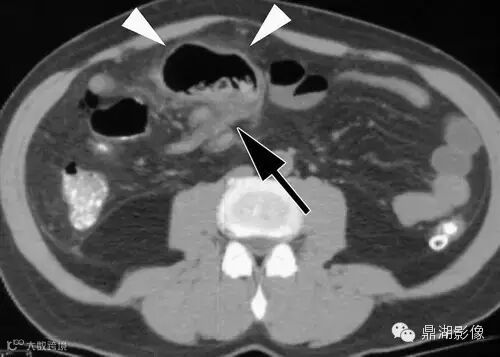

18岁男性,腹痛,定位模糊,无直肠出血。

典型的位置位于下腹部(少数盆腔内)中线附近(67%),尤其是肚脐附近是其典型位置,病变与肚脐关系密切尤其是可见纤维索相连高度提示为Meckel's 憩室炎。发生于回肠肠系膜对侧,距回盲瓣50-60cm以内。

肠系膜炎性改变常较显著,表现为系膜密度增高及周围脂肪内条索状影,部分可伴腹水。

憩室壁常增厚,增强后绝大多数可见粘膜面强化。